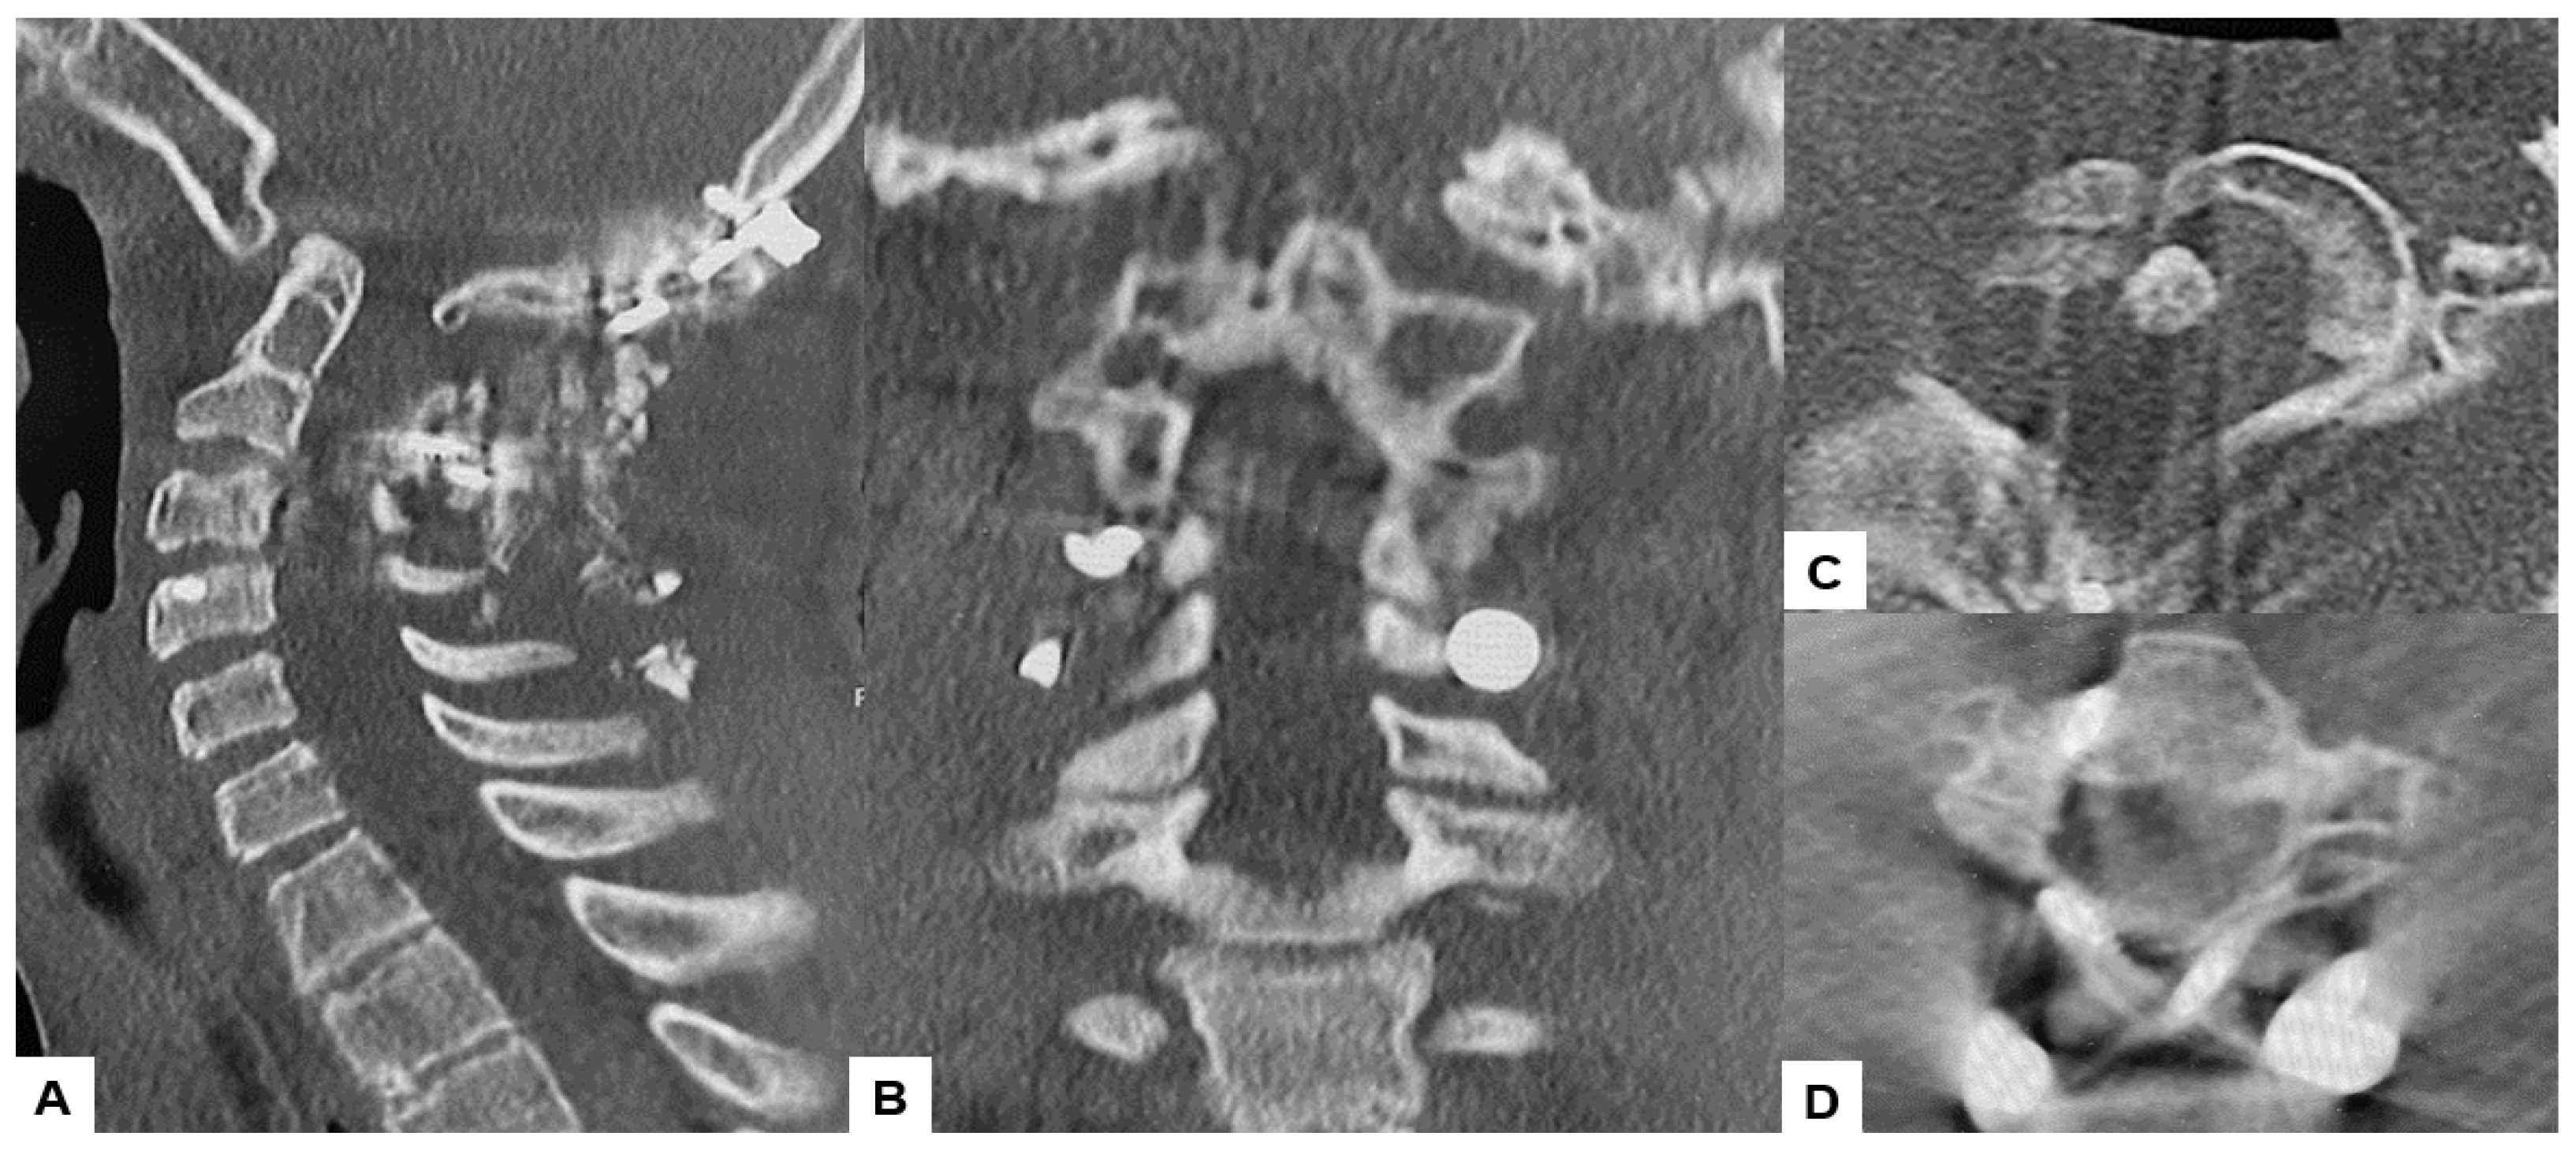

2.6. One Year Follow-Up

Postoperative MRI indicated excellent spinal cord decompression (Figure 15).

Figure 15.

Follow-up images, (A) Mid sagittal T1-weighted MR imaging, (B) Mid sagittal T2-weighted MR imaging. (C) Axial T2-weighted MR imaging at C1, (D) Axial T2-weighted MR imaging at C2. The spinal cord was adequately decompressed.

Surgically, the patient was successfully treated, with a surgical time of 139 min and an estimated blood loss of 180 mL. During the one-year follow-up, manual muscle testing results and sensory function tests indicated almost full recovery in both bilateral arms (MMT 5). The patient is now walking smoothly without any gait disturbance, and the cervical Japanese Orthopedic Association score improved from 9/17 to 16/17. Postoperative radiographs demonstrated excellent spinal cord decompression, with no loss of reduction or malalignment. The cervicomedullary angle (CMA) postoperatively measured 130 degrees. Furthermore, there were no major or severe complications reported.